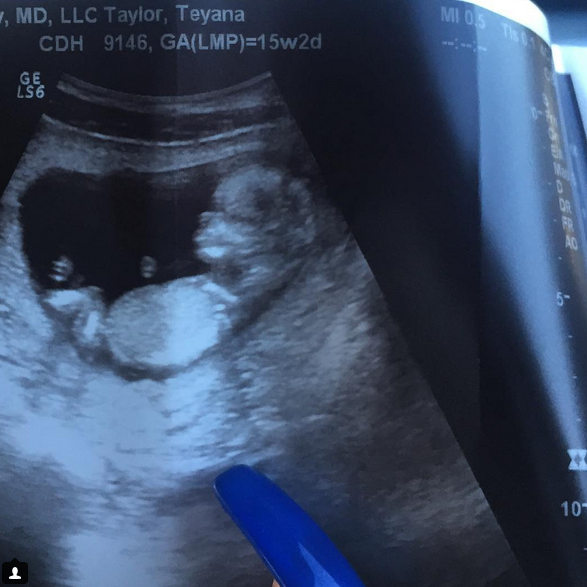

Iman Shumpert & Teyana Taylor, 첫 아이 생기다

Iman Shumpert는 NBA, 그중에서도 클리블랜드 캐벌리어스를 좋아하는 분이라면 잘 알만한 프로 농구 선수인데요. 그와 그의 여자친구이자 G.O.O.D Music 소속 가수 Teyana Taylor 사이에 첫 아이가 생겼다고 합니다. 아이의 출생예정일은 2016년 1월 중순이라고 합니다. Iman Shumpert는 인스타그램에 ‘이렇게 사람들에게 알리게 돼 너무 행복하다. Teyena Taylor에게도 너무 고맙다.’ 라고 올렸으며, Teyana Taylor는 남자친구의 인스타그램 캡처 사진과 ‘나도 사랑해’라는 글을 함께 올렸다고 합니다. 정말 깨가 쏟아지네요.